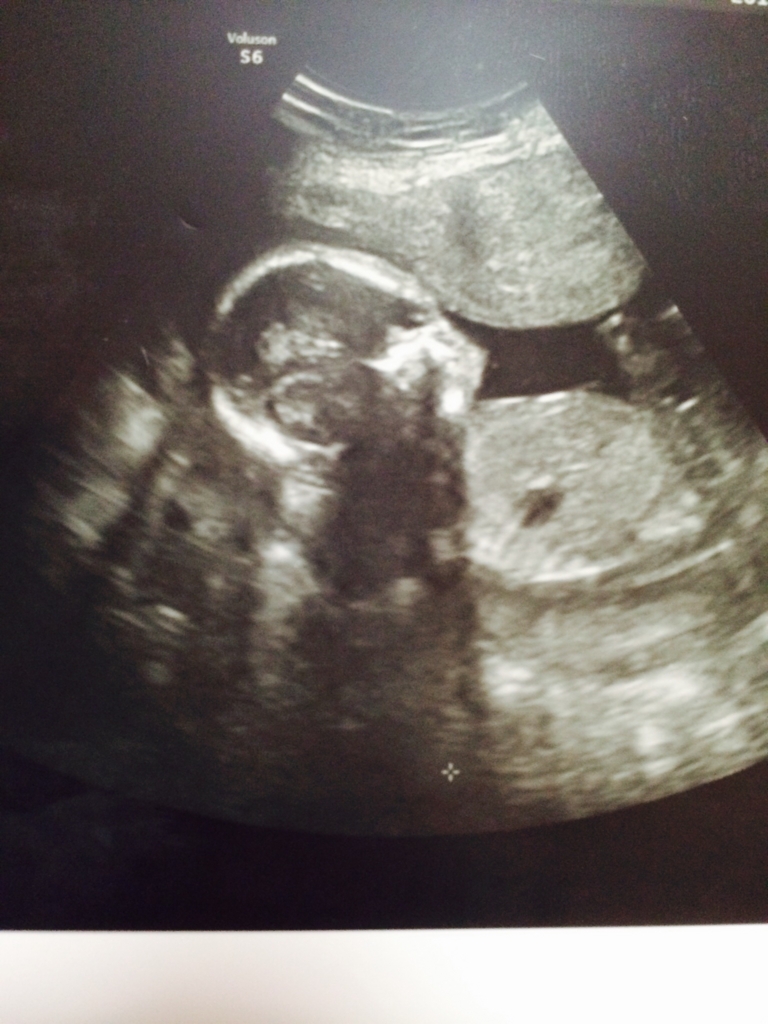

もちろん、エコー画像にありますように1人ですけどね(^ ^)汗